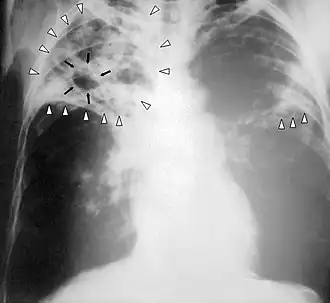

- Chest X-Ray - pericardial calcification (common but not specific), pleural effusions are common findings.[11]